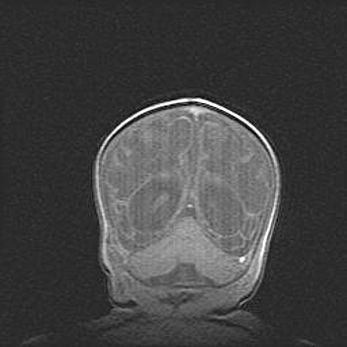

Сообщающаяся гидроцефалия. Кистозная энцефаломаляция головного мозга.

Возраст: 3 месяца 4 дня

Вес: 3100 г

Пол: женский

Окружность головы: 34 см

Срок гестации: 31 неделя

Кистозная энцефаломаляция головного мозга - одна из форм поражения головного мозга в детском возрасте. Характеризуется возникновением множественных и распространённых кист в коре, белом веществе и подкорковых образованиях головного мозга у плодов, новорождённых и детей раннего возраста. Развитие кистозной энцефаломаляции связано с внутриутробной асфиксией и гипотонией, родовой травмой, тромбозом синусов, пороками развития сосудов, инфекциями, сепсисом и другими причинами. Наиболее значимые инфекционные агенты: вирусы простого герпеса, цитомегалии, краснухи, токсоплазмы, энтеробактерии, золотистый стафилококк и другие.